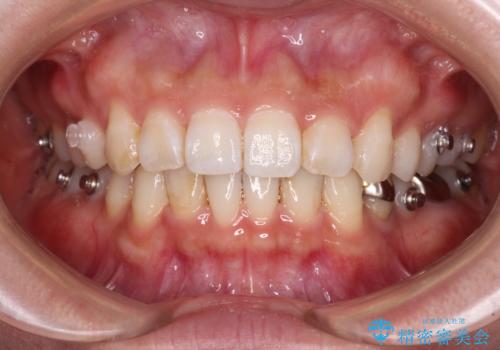

- 前歯のデコボコと深い咬み込みを気にして来院された患者様です。

インビザラインを用いて、前歯の叢生を解消するとともに、深い咬み合わせ(ディープバイト)を改善していくこととしました。

奥歯を後方に直立させることで深い咬み合わせを改善を図り、隠れていた下顎前歯が見えるほどになりました。